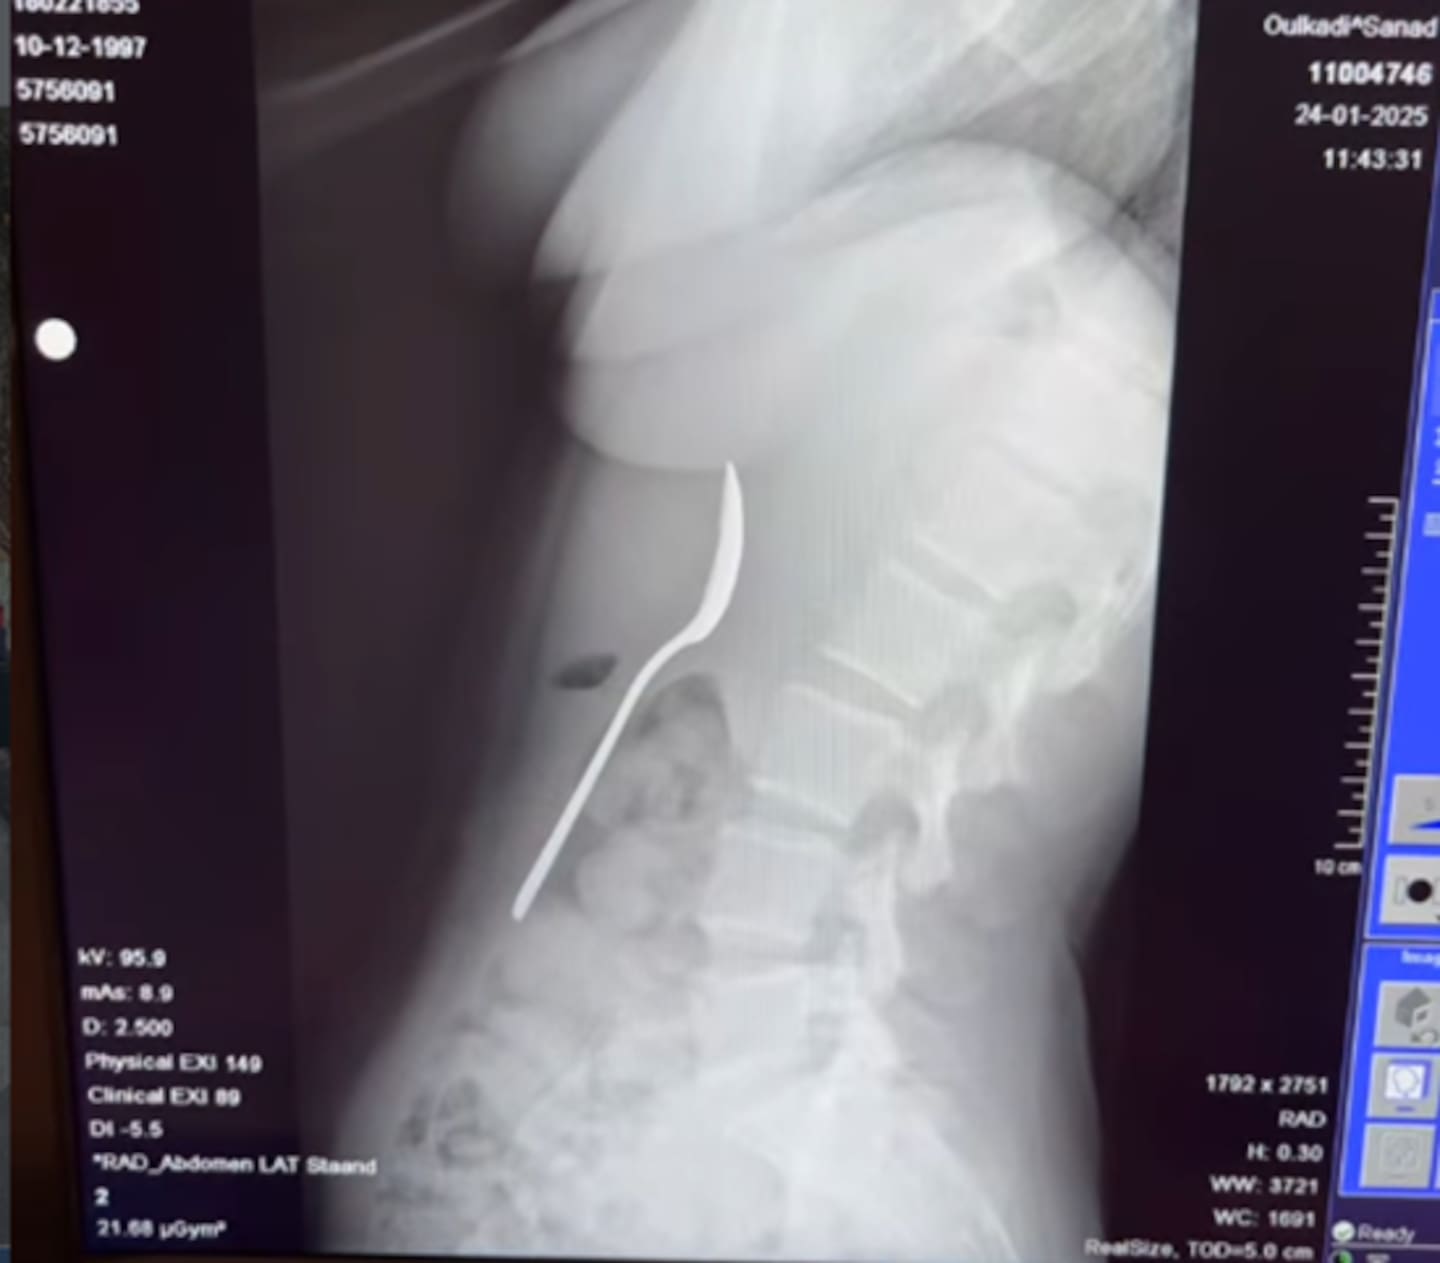

A woman was left in a panic after she swallowed a 17cm spoon when her dog jumped on her as she was eating yoghurt.

“There was a 17cm spoon in my stomach.

Amelinckx described feeling “truly terrified” trying to sleep that night as she felt the spoon moving between her ribs.

Two days later, Amelinckx underwent minor surgery.

“They had to rotate it in my stomach, which caused a small gastric haemorrhage.